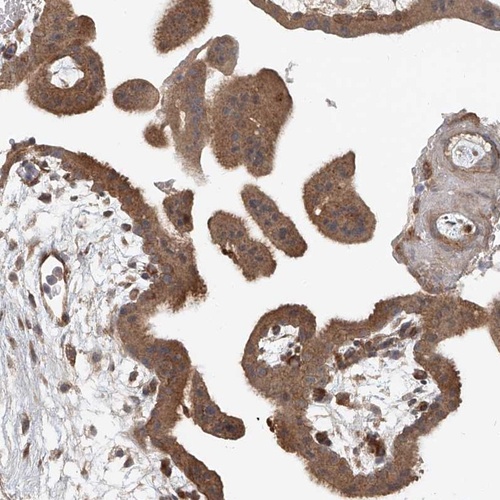

Immunohistochemical staining of human placenta shows cytoplasmic positivity in trophoblastic cells.